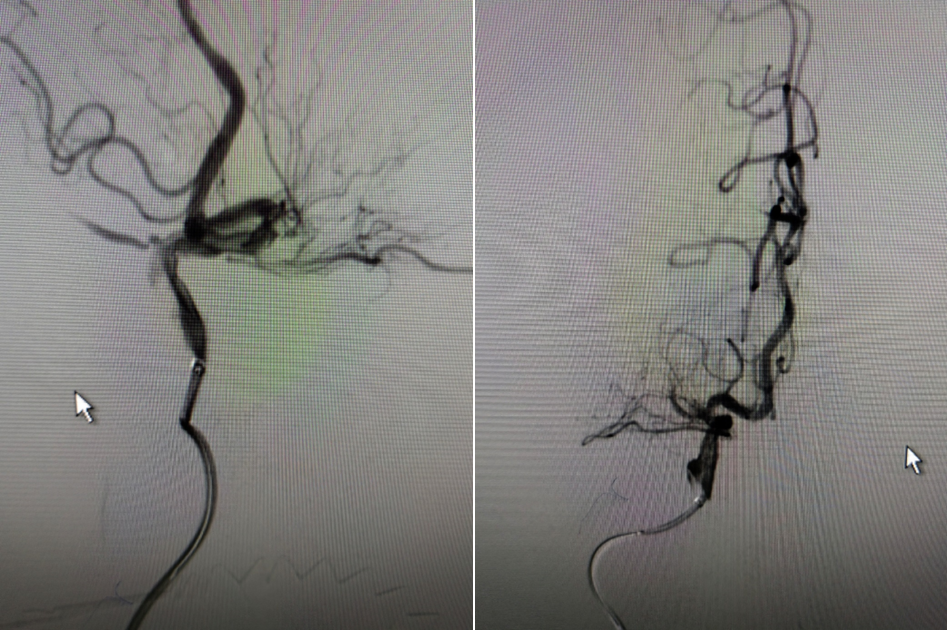

6F-远端通路导管在黑泥鳅导丝的指引下通过闭塞段送至眼动脉段,造影证实闭塞段在海绵窦段,予以ADPAT技术取出少量血栓,仍未开通。

导丝怎么扩【载药时代 球扩天下】NOVA DES®颅内药物洗脱支架在大脑中动脉重度狭窄的应用二例!_https://www.jmylbn.com_新闻资讯_第7张

导丝怎么扩【载药时代 球扩天下】NOVA DES®颅内药物洗脱支架在大脑中动脉重度狭窄的应用二例!_https://www.jmylbn.com_新闻资讯_第8张

通过微导管释放取栓支架,SWIM取栓技术,可见海绵窦段狭窄,前向血流不稳定。